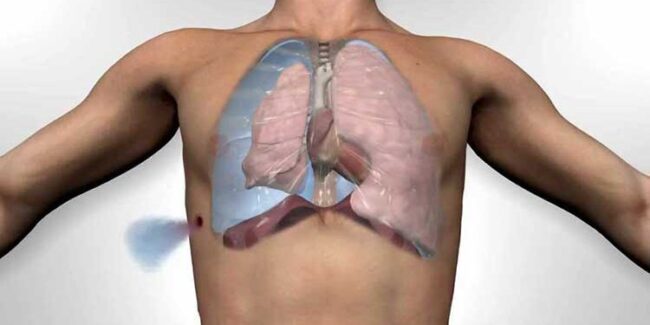

Introduction Recurrent pleural effusions (RPEs) are defined as pleural effusions that recur despite optimal therapy for the underlying etiology of the effusions and typically require multiple thoracenteses or a more definitive therapeutic modality to prevent a recurrence. Indwelling pleural catheters (IPCs) have emerged in the past decade as a very effective modality to treat and…